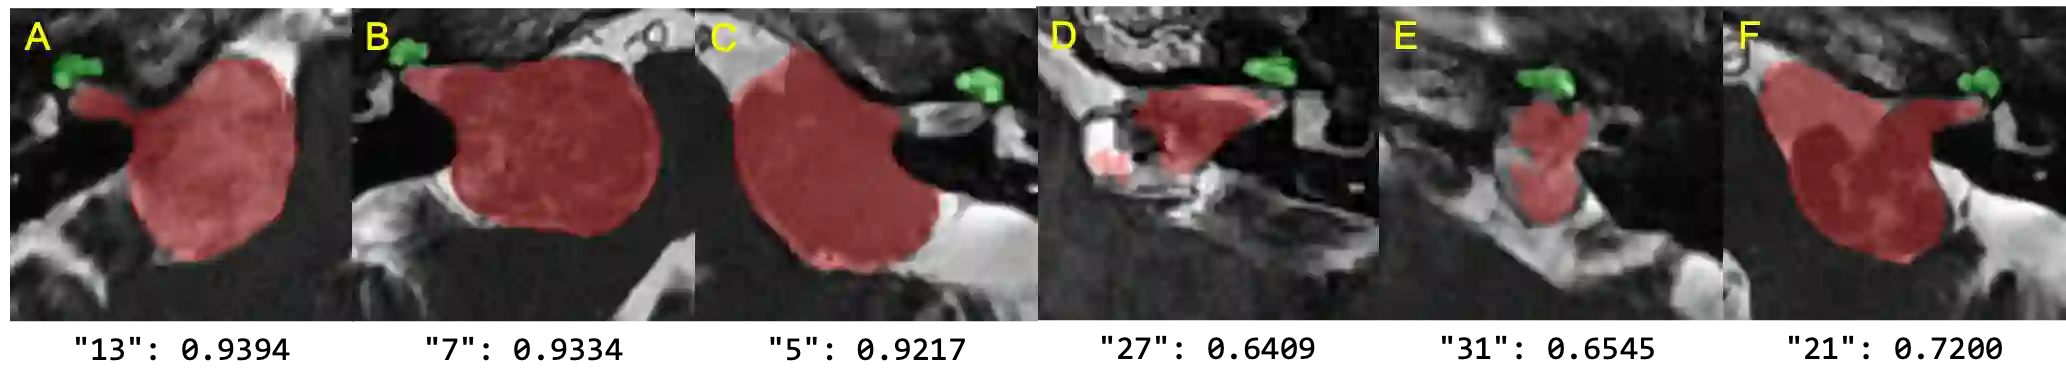

Automatic methods to segment the vestibular schwannoma (VS) tumors and the cochlea from magnetic resonance imaging (MRI) are critical to VS treatment planning. Although supervised methods have achieved satisfactory performance in VS segmentation, they require full annotations by experts, which is laborious and time-consuming. In this work, we aim to tackle the VS and cochlea segmentation problem in an unsupervised domain adaptation setting. Our proposed method leverages both the image-level domain alignment to minimize the domain divergence and semi-supervised training to further boost the performance. Furthermore, we propose to fuse the labels predicted from multiple models via noisy label correction. Our results on the challenge validation leaderboard showed that our unsupervised method has achieved promising VS and cochlea segmentation performance with mean dice score of 0.8261 $\pm$ 0.0416; The mean dice value for the tumor is 0.8302 $\pm$ 0.0772. This is comparable to the weakly-supervised based method.